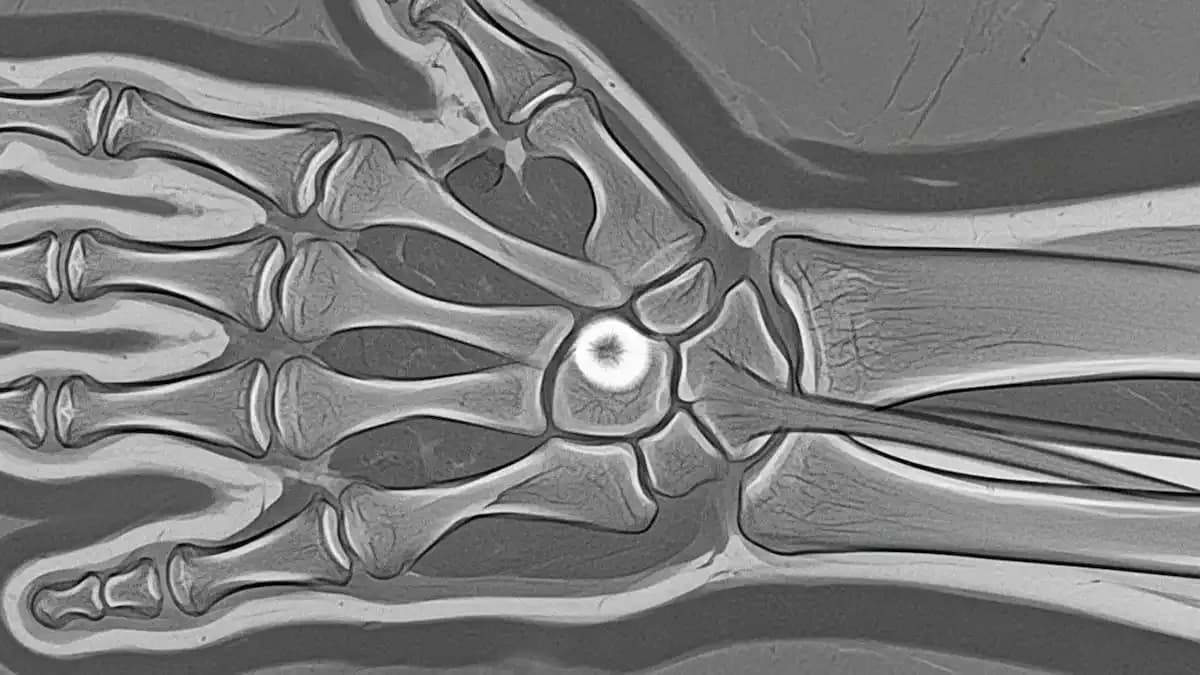

Exames de imagem como radiografias ajudam a entender melhor a anatomia envolvida e guiar as decisões terapêuticas.